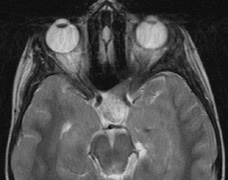

Lisch nodules are hamartomas (a tumor involving only those tissue elements normally found at the involved site) of the iris pigment epithelium. They are dome-shaped discrete lesions, are typically light brown in color, and may also be found in the angle.38 Lisch nodules appear earlier (33% at 2.5 years, 50% at 5 years of age)39 than neurofibromas. They are benign and can help to confirm diagnosis in children who may have café au lait spots as the only other clinical finding. Lisch nodules are present in nearly all adults with NF139,40 but are rare in NF2 (Fig. 3).41,42 Diffuse nodular iris nevi (also known as iris mamillations) should not be confused with Lisch nodules. Its clinical significance is not well established.43,44

Fig. 3. Neurofibromatosis type 1: Lisch nodules. These are hamartomas of the iris pigment epithelium. Lisch nodules are present in nearly all adults with NF1,39,40 but are rare in NF2.41,42

2. At least two Lisch nodules (Fig. 3)

3. At least five café au lait spots ≥ 5 mm before puberty or at least 6 café au lait spots ≥ 15 mm after puberty (Fig. 1)